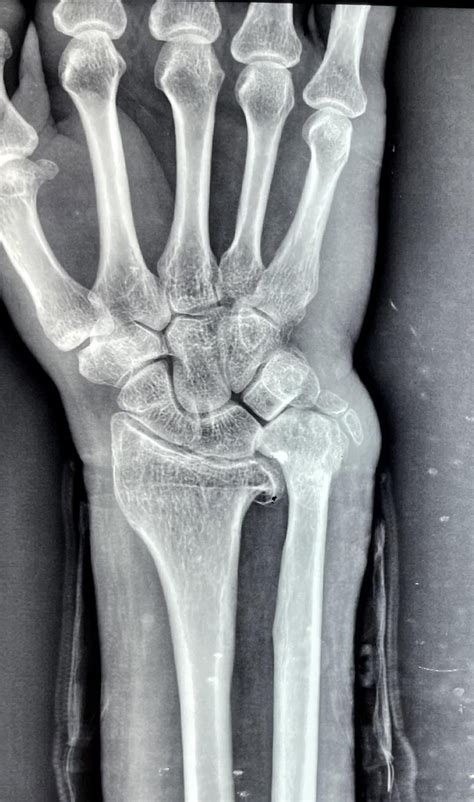

Imaging is equally vital. Standard X-rays, particularly those taken in a neutral position, help clinicians measure the ulnar variance. In more complex cases, an MRI is ordered to evaluate the extent of TFCC damage, cartilage wear on the lunate, or subchondral bone edema, which is the "bruising" of the bone caused by persistent impaction.